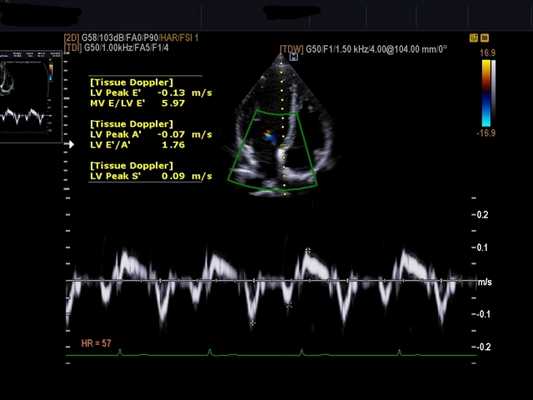

Импульсно-волновой, непрерывно-волновой, тканевой допплер и изображения цветного допплеровского потока на эхокардиографии является полезным для определения сердечного выброса, давления в легочной артерии, степени митральной регургитации, давления наполнения ЛЖ и механической диссинхронии. Сердечный выброс обычно измеряется с использованием оценки интегральной скорости кровотока в аорте в соотношении с ее диаметром. Диастолический модель потока трансмитрального заполнения желудочка, тканевая допплерография и цветовой М-режим обеспечивает понимание давления наполнения ЛЖ, а также диастолической функции. На эхокардиографии в режиме тканевого допплера оба пика систолической скорости митрального кольца (S) и скорости раннего диастолического наполнения (Е) уменьшаются при дилатационной кардиомиопатии.

Эходопплерография и цветное допплеровское изображение дают важную гемодинамическую информацию, которая поможет в оценке давления наполнения ЛЖ, стратегии управления и прогноз. Пациенты с компенсацией по гемодинамике с практически нормальным ударным объемом сердечного выброса и нарушением релаксации в диастолу (1 класс диастолической дисфункции). Пациенты, которые имеют более тяжелые формы декомпенсированной кардиомиопатии снижается ударный объем (интеграл линейной скорости кровотока уменьшается) и имеется ограничительный паттерн диастолического наполнения ЛЖ (класс 3-4 диастолической дисфункции) из-за снижения соответственно притока и увеличения давления наполнения ЛЖ. Развитие диастолической дисфункции с нарушением паттерна ограничительной релаксации при диастолическом заполнении было элегантно продемонстрировано на животных моделях с тахи-индуцированными кардиомиопатиями. Различные критерии переменных диастолического наполнения ЛЖ, которые имеют хорошую корреляцию с легочным капиллярным давлением заклинивания, имеют дополнительную прогностическую ценность вместе теми показателями, которые обеспечивают расчет фракции выброса. Чем короче время изоволюмического расслабления (ДТ) (т. е., более ограничительный характер диастолического наполнения) и выше, Е/Е' (т. е. выше давление заклинивания в легочных капиллярах), тем хуже прогноз. В качестве примера, если пациент лечится от сердечной недостаточности, нарушение диастолического наполнения ЛЖ становится менее строгим и ДТ возрастает. Сохранение ограничительного наполнения после терапии связано с высоким уровнем смертности и определяет показания к трансплантации сердца. У пациентов с обратимой дисфункцией ограничительного заполнения имеют высокую вероятность улучшения и отличное выживание.